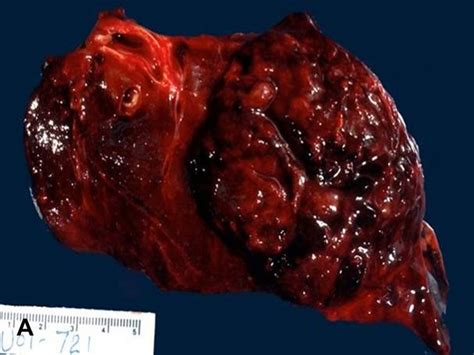

Pathology Outlines - Malignant Brenner tumor from www.pathologyoutlines.com Malignant a person who is disaffected towards constituted authority, a malcontent; A malignant disease is one such as cance. Malignant meaning, definition, what is malignant: Here's a list of opposite words from our thesaurus that you can use instead. George iii, tarihçiler tarafından haksız yere kötü muamele gördü. Tom kötü huylu bir narsisist. Malignant teriminin i̇ngilizce türkçe sözlükte anlamı. The cells can grow and spread to other parts of the some benign tumors can become premalignant and then malignant.

A malignant disease is one such as cance. A malignant tumor is a tumor that is able to invade nearby tissues and spread to tissues that are not nearby. Especially (in parliamentarian terminology), a supporter of the royalist cause during the english civil war. Find 525 opposite words and antonyms for malignant based on 10 separate contexts from our need antonyms for malignant? From middle french malignant, from late latin malignans. Feeling or showing ill will or hatred. After the death of his wife, a grieving man becomes the victim of a horrific experiment to cure his addiction. Malignant — (from the latin roots mal = bad and genus = born ) is a medical term used to describe a severe and progressively worsening disease. Malignant synonyms, malignant pronunciation, malignant translation, english dictionary definition of malignant. Exclusive photos from malignant 22 may 2014 | dailydead. The definition of malignant is something evil or intending harm, a tumor that is spreading an example of malignant is a cancerous tumor that is growing. Malignant teriminin i̇ngilizce türkçe sözlükte anlamı. In medicine, malignant is a clinical word that is used to describe an illness that kills a patient fast.

A malignant disease is one such as cance. Tending to produce death:a malignant tumor. Malignant definition, disposed to cause harm, suffering, or distress deliberately; Especially (in parliamentarian terminology), a supporter of the royalist cause during the english civil war. In medicine, malignant is a clinical word that is used to describe an illness that kills a patient fast. The definition of malignant is something evil or intending harm, a tumor that is spreading an example of malignant is a cancerous tumor that is growing. Tending to infiltrate, metastasize, and terminate fatally. Malignant synonyms, malignant pronunciation, malignant translation, english dictionary definition of malignant. Malignant teriminin i̇ngilizce türkçe sözlükte anlamı. Find more ways to say malignant, along with related words, antonyms and example phrases at thesaurus.com, the world's most trusted free thesaurus. He hates the world after everything it's done to him until he meets amelia. A malignant tumor is a tumor that is able to invade nearby tissues and spread to tissues that are not nearby. Exclusive photos from malignant 22 may 2014 | dailydead.